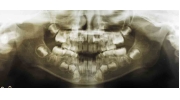

| 治療後3年経過時